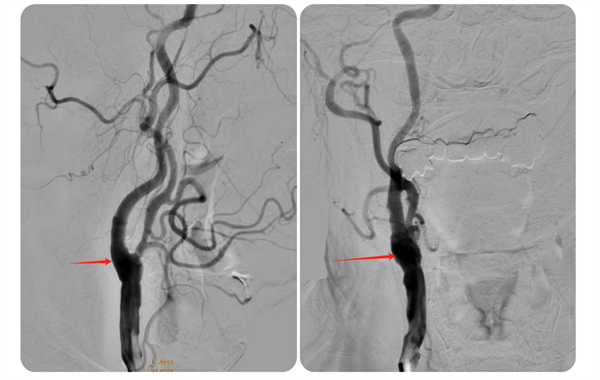

近日,我院神经外科收治了一名74岁高龄且伴有多年高血压、糖尿病史的高危患者何先生(化名)。何先生此前已接受过右侧椎动脉、左侧锁骨下动脉支架植入术,但近期因头晕、左侧肢体乏力等症状再次入院。经过详细检查,医生发现何先生右侧颈内动脉起始部存在重度狭窄,狭窄率高达75%,情况危急。

▲术前脑血管造影

术后,何先生顺利苏醒,回到神经外科病房进行监护治疗,术后7天伤口愈合良好拆线出院。8月何先生来我院复查,DSA检查提示右侧颈动脉狭窄已完全恢复并无再狭窄,头晕及左侧肢体乏力症状也完全缓解了。

▲术后狭窄完全解除